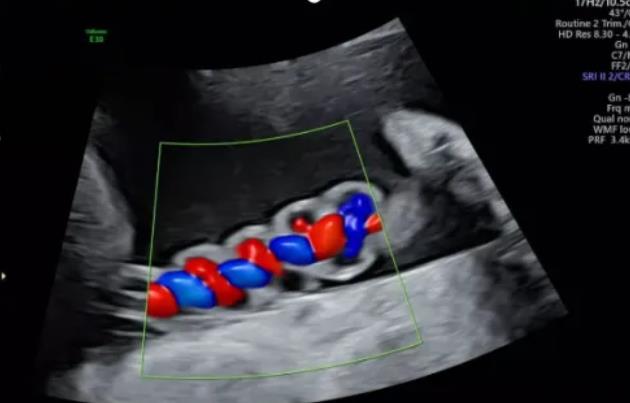

漯河市中醫(yī)院健康科普:超聲檢查之臍帶螺旋

聲像圖特征:臍動脈表現(xiàn)為過度螺旋,臍血管變細(xì),縱切面呈“麻花狀”,橫切面呈“鼠眼狀”;

2、臍帶螺旋過松

聲像圖特征:胎兒臍帶縱切面示血管呈平行排列,螺旋稀少,彩色多普勒血流成像示臍帶血管內(nèi)充滿的紅藍(lán)血流呈平行排列,麻花狀螺旋消失。